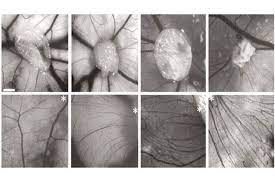

قیمت: 32٬000 تومان - دسته بندی فایل: پاورپوینتپاورپوینت بیماریهای منتقله از راه جنسی

فروش ویژه پاورپوینت حرفه ای بیماریهای منتقله از راه جنسی با تخفیف استثنایی فقط 54 هزار تومان تعداد اسلاید: 19 اسلاید